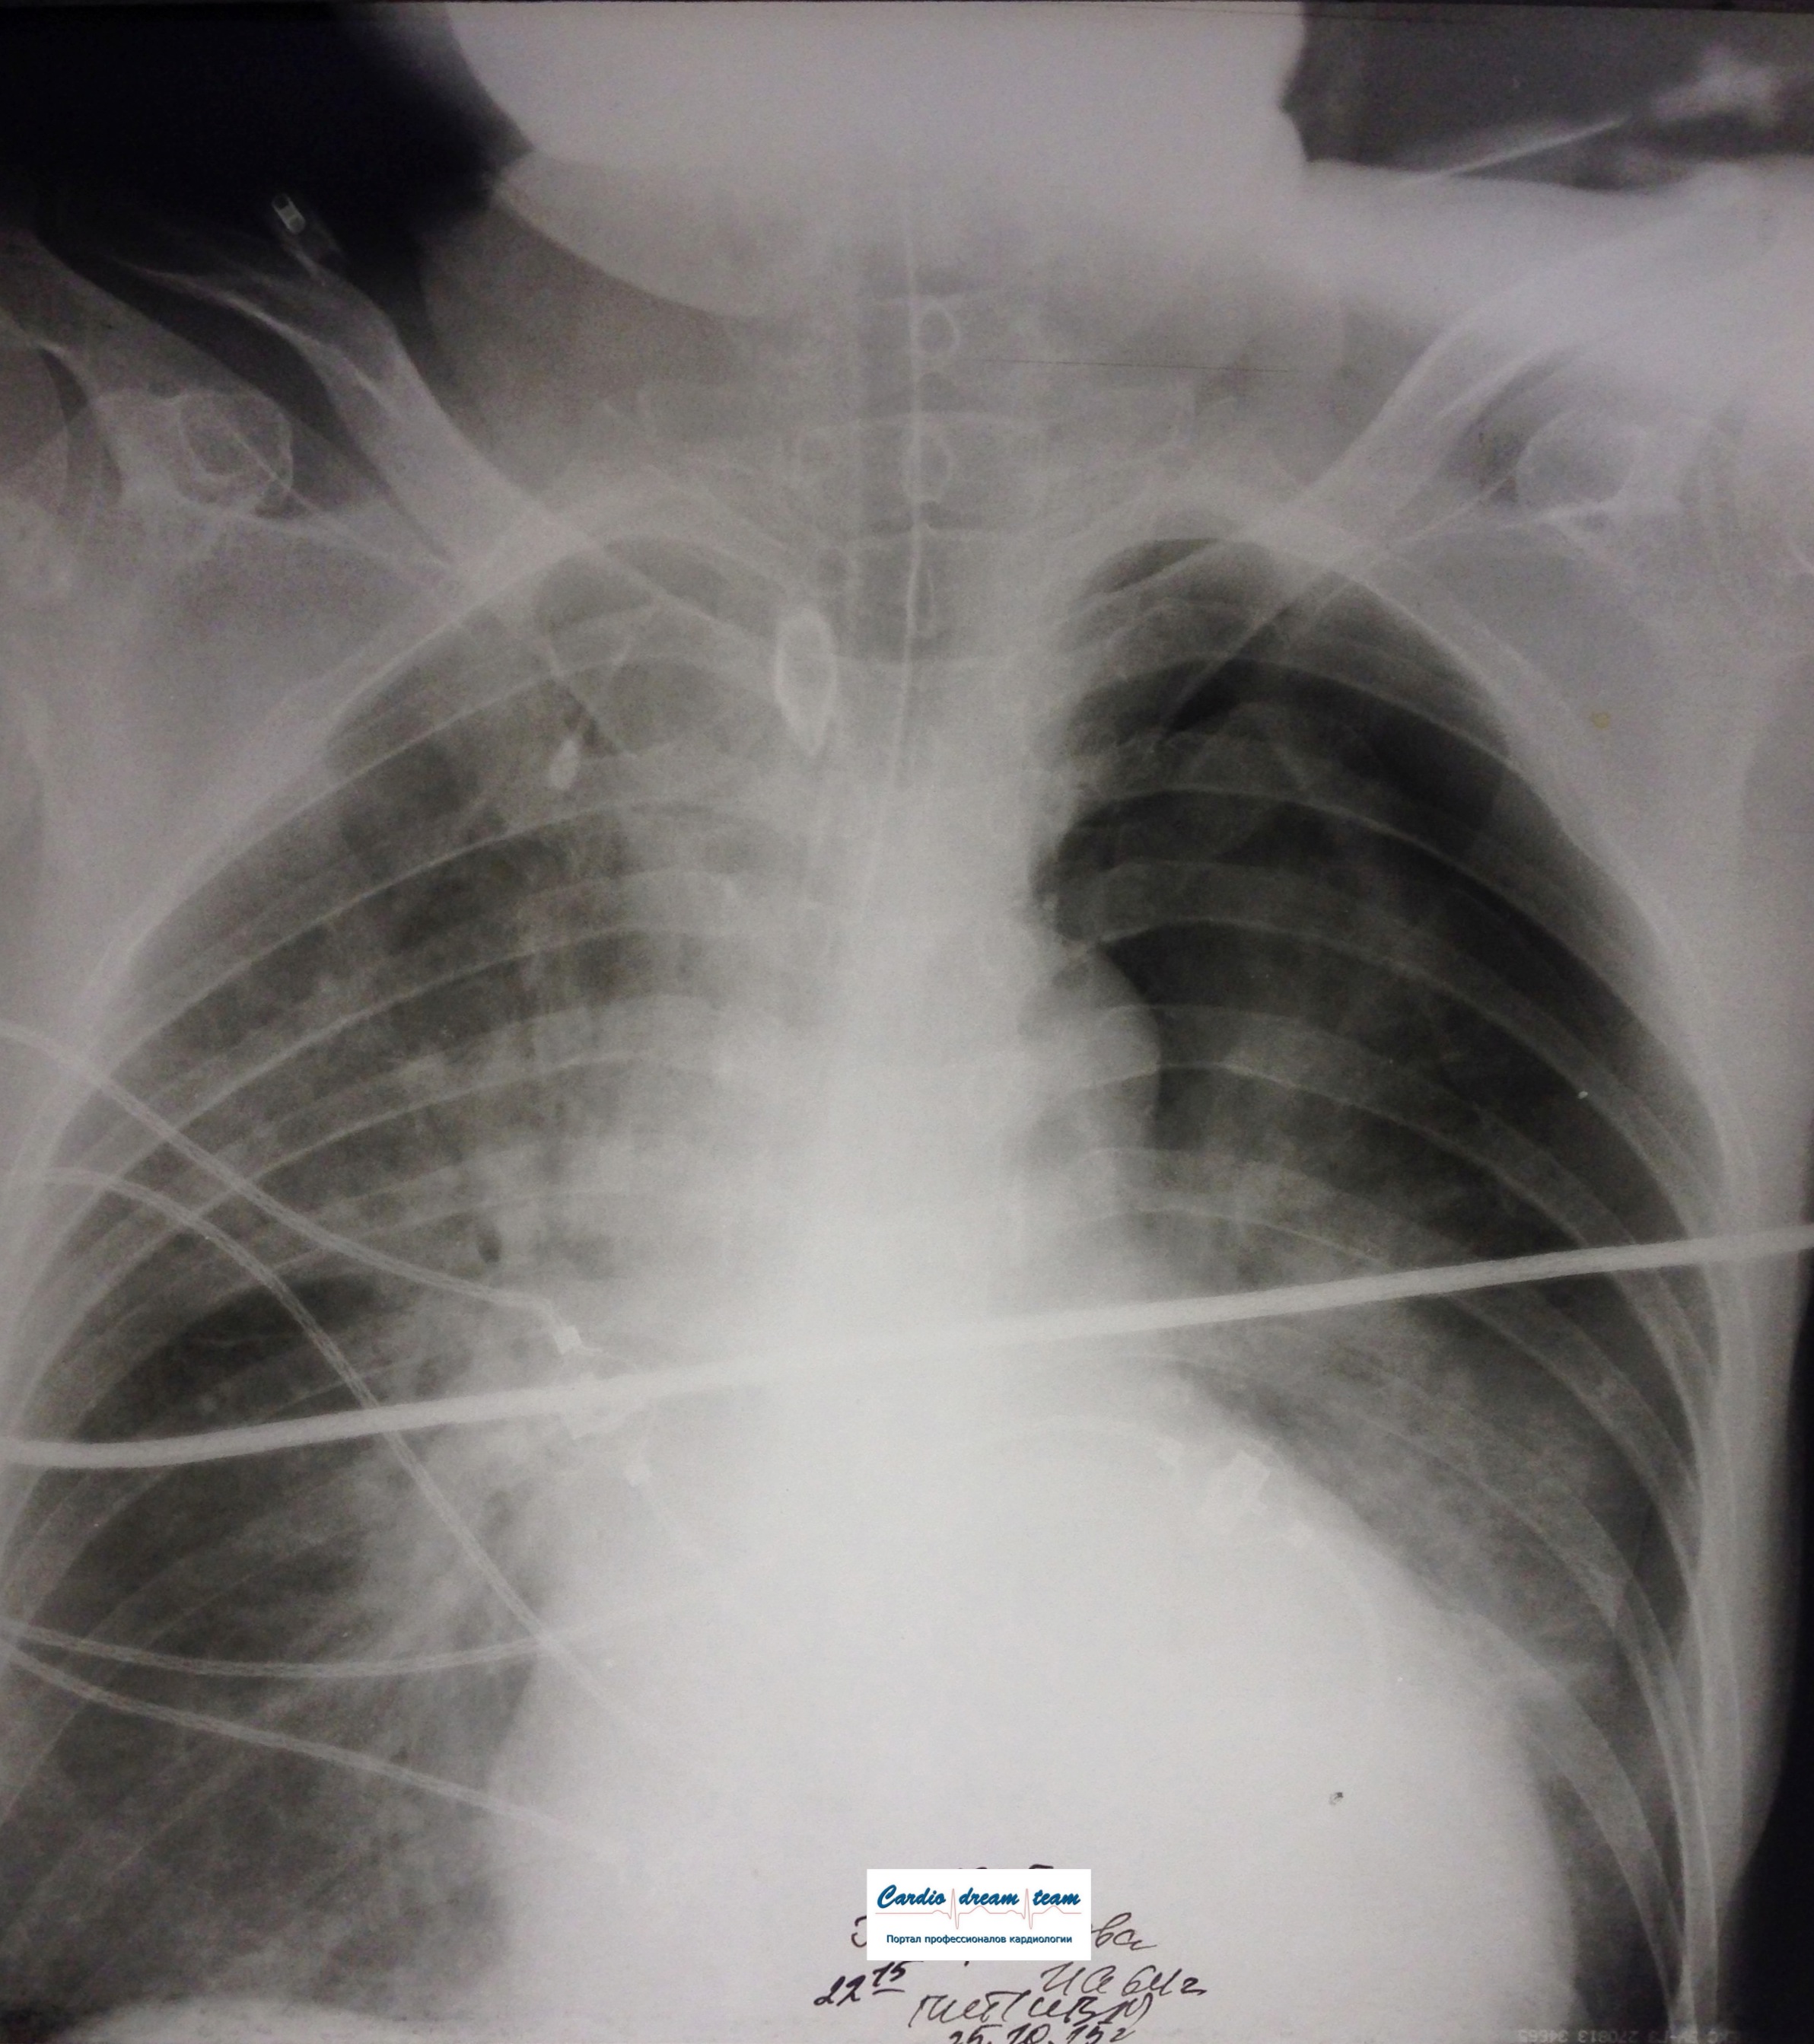

ИССЛЕДОВАНИЕ ОРГАНОВ ГРУДНОЙ КЛЕТКИ Дата 01-ОКТ-15 время 11.30 ОПИСАНИЕ: Проведена рентгенография органов грудной клетки в прямой проекции, положение сидя, условия ПИТ, Р-контроль Легочные поля: Справа легкое расправлено не полностью, апикально до 3го ребра прослеживается свободный газ в плевральной полости. Тень дренажа справа. Тень подключичного катетера в проекции ВПВ. Легочный рисунок: сгущен справа в прикорневой зоне, диффузно деформирован Корни: малоструктурны, обогащены Синусы: нечеткие Сердце: широко лежит на диафрагме (позиционно) ЗАКЛЮЧЕНИЕ: Течение правостороннего пневмоторакса, положительная Р-динамика. Состояние дренирования правой плевральной полости. Р-признаки полнокровия сосудов МКК. Пневмосклероз. Р-контроль .────────────────────────────────────────────────────────────────────── ИССЛЕДОВАНИЕ ОРГАНОВ ГРУДНОЙ КЛЕТКИ Дата 02-ОКТ-15 время 1015 ОПИСАНИЕ:

Проведена рентгенография органов грудной клетки в прямой проекции, положение полусидя, условия ПИТ, Р-контроль Легочные поля: Отрицательная динамика: правое легкое поджато к корню. Тень средостения резко смещена влево. Выраженная подкожная эмфизема мягких тканей грудной клетки справа. Тень подключичного катетера в проекции ВПВ. Легочный рисунок: диффузно деформирован за счет пневмосклероза, сгущен справа Корни: тень средостения смещена влево Синусы: нечеткие Сердце: широко лежит на диафрагме (позиционно) ЗАКЛЮЧЕНИЕ: Правосторонний пневмоторакс, отрицательная Р-динамика. Эмфизема мягких тканей грудной клетки. Пневмосклероз. Р-контроль.